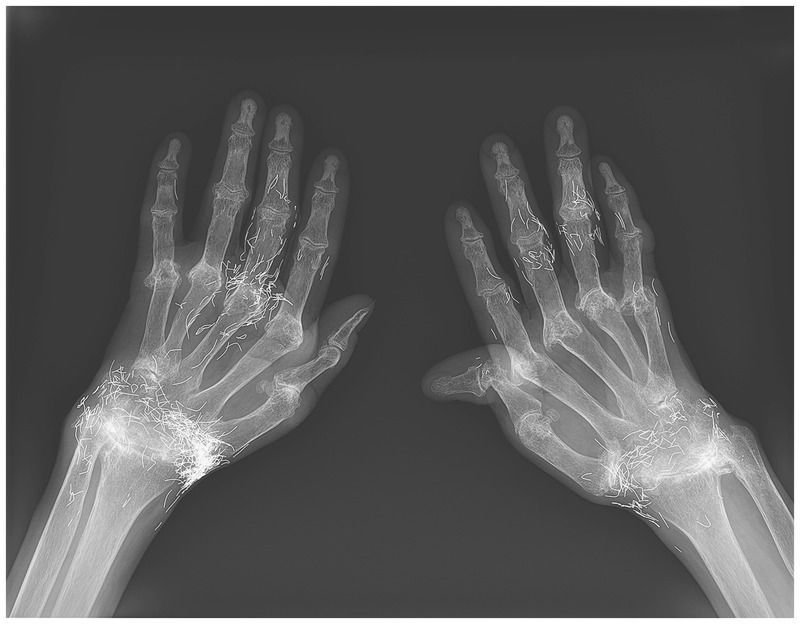

A 58-year-old woman presented to the rheumatology clinic with long-standing joint pain and deformities of both hands and feet. Her joint symptoms had begun when she was approximately 18 years of age, after which she had received treatment with ibuprofen and gold thread acupuncture (the insertion of small pieces of sterile gold thread with the use of acupuncture needles). Ten years before the current presentation, she had received a diagnosis of rheumatoid arthritis, which had been confirmed by laboratory test results that showed a rheumatoid factor of 628.7 IU per milliliter (normal value, <14) and an anticitrullinated protein antibody level of 170.8 U per milliliter (normal value, <5). Plain radiographs of both hands that were obtained at the current presentation showed severe joint damage and deformity of the wrists and proximal interphalangeal and metacarpophalangeal joints, with numerous short gold threads surrounding the joints. In East Asia and globally, acupuncture — including gold thread acupuncture — has long been used to treat joint pain. Oral and injectable gold preparations are also sometimes used. After the initial diagnosis of rheumatoid arthritis, the patient had been treated with the combination of methotrexate and leflunomide. When she was referred to our hospital, we changed her treatment regimen to a combination of methotrexate and abatacept, and she underwent surgery for the foot deformities, which led to a substantial reduction in joint pain.